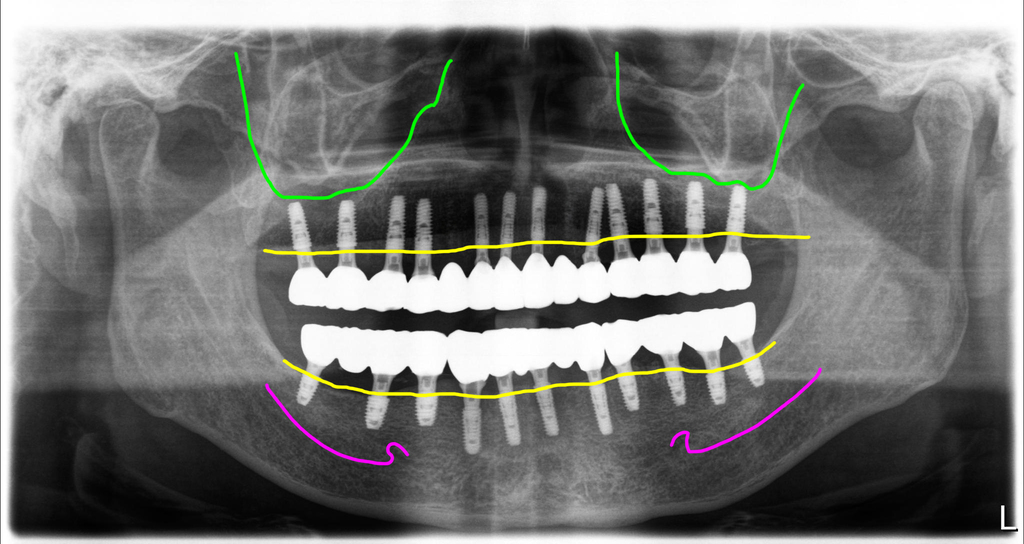

전체임플란트 치료완료

치료전 상태가 안 좋았지만 이제는 정상적인 오버젯을 가진 아름다운 모양으로 치료가 완료되었습니다. 치열의 구조가 좋으면 심미적으로 우수한 것은 당연하고 기능적으로도 훨씬 좋고 이후 장기간 사용시 문제가능성도 줄어들게 됩니다.

최종보철 세팅후 파노라마 마진핏이 좋습니다.

지대주와 지르코니아 디자인을 동시에 진행하고 동시에 세팅하는 방식이라 지대주와 지르코니아크라운의 마진핏이 아주 좋습니다.

그리고 치아와 치아사이에 치간치솔을 사용할 수 있도록 디자인되었고 세팅시 환자에게 치솔질교육을 합니다.